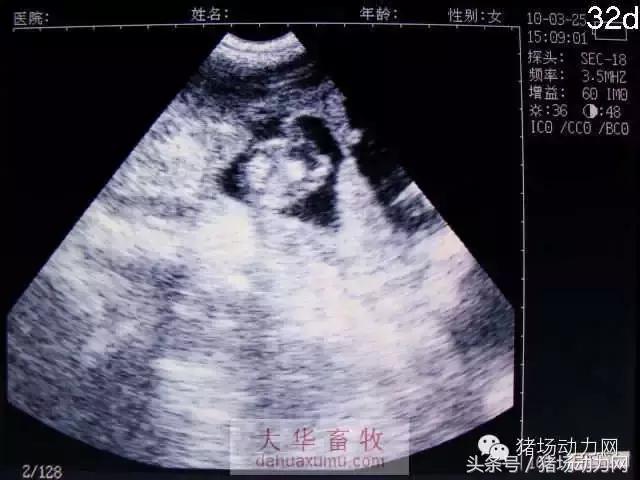

以下为怀孕母猪21天到90天之内的变化图:

32天